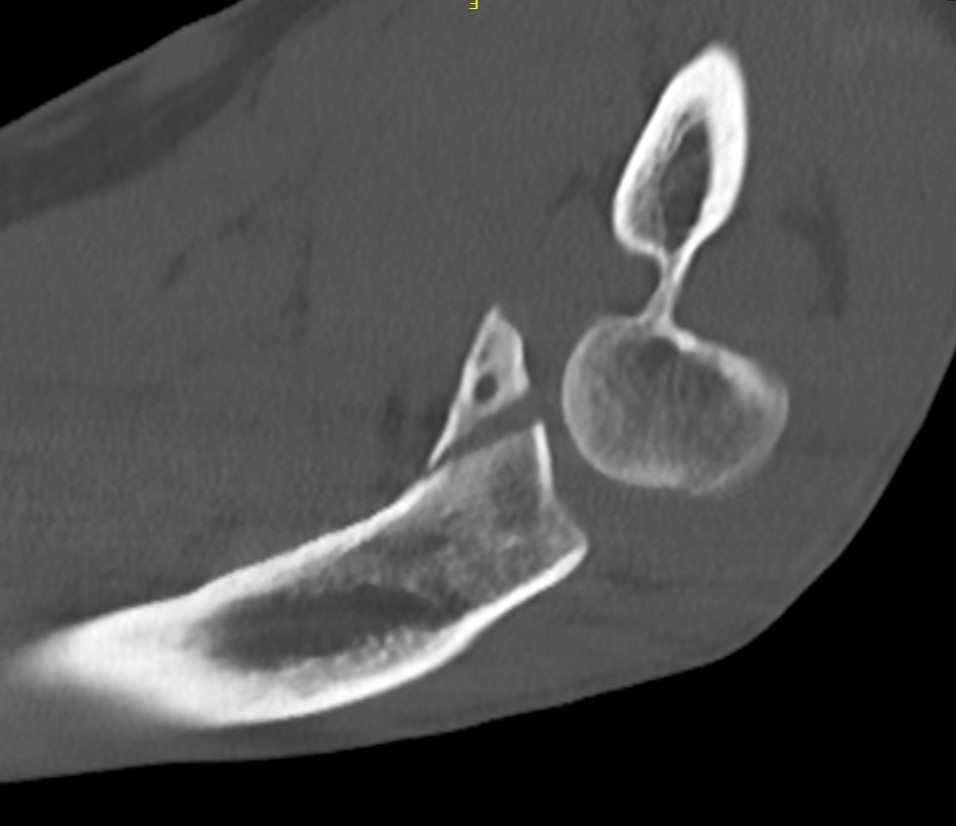

Overstuffing

| Lesser sigmoid notch | Symmetry of ulnohumeral joint |

|---|---|

|

Radial head shoulder articulate with lesser notch

Ensure no gapping of lateral ulnohumeral joint |

- cadaveric study

- increased medial ulno-humeral joint line gapping with overlengthening of 6 or 8 mm

- increased lateral ulno-humeral joint line gapping with overlengthening of 2 mm